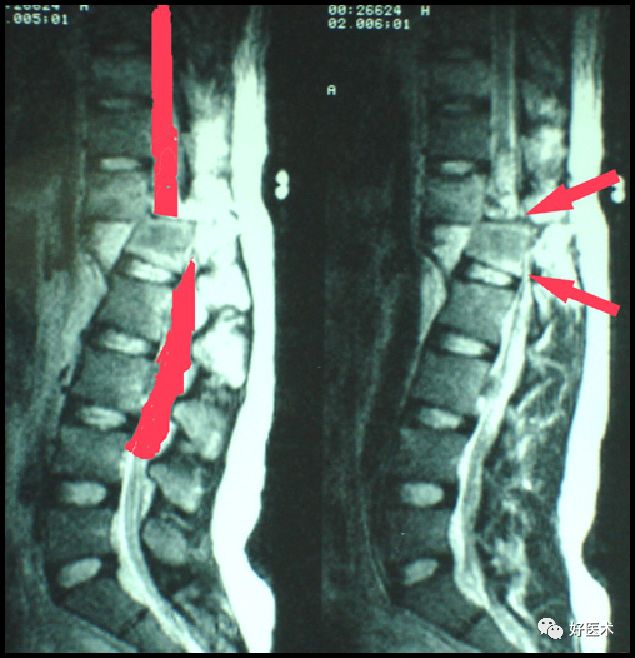

脊柱为人体躯干的中轴,保护脊髓神经,躯体活动可引起脊柱的活动。长期卧床易发生压疮,脊柱骨折脱位或手术病人,由于脊柱稳定性差,有继续损伤的危险,不正确的体位改变可导致脊髓损伤、内固定松脱等严重并发症。

护士在翻身时,应采用轴性(滚桶式)翻身,防止脊柱前屈或扭曲;当翻身至对侧时,对侧及背部必须有良好的支撑。